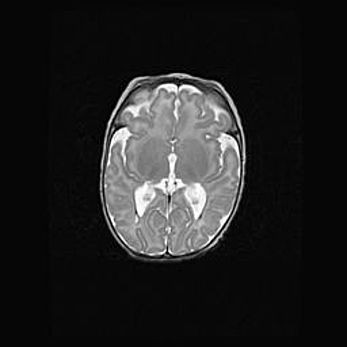

Сообщающаяся гидроцефалия. Кистозная энцефаломаляция головного мозга.

Возраст: 3 месяца 4 дня

Вес: 3100 г

Пол: женский

Окружность головы: 34 см

Срок гестации: 31 неделя

Кистозная энцефаломаляция головного мозга - одна из форм поражения головного мозга в детском возрасте. Характеризуется возникновением множественных и распространённых кист в коре, белом веществе и подкорковых образованиях головного мозга у плодов, новорождённых и детей раннего возраста. Развитие кистозной энцефаломаляции связано с внутриутробной асфиксией и гипотонией, родовой травмой, тромбозом синусов, пороками развития сосудов, инфекциями, сепсисом и другими причинами. Наиболее значимые инфекционные агенты: вирусы простого герпеса, цитомегалии, краснухи, токсоплазмы, энтеробактерии, золотистый стафилококк и другие.